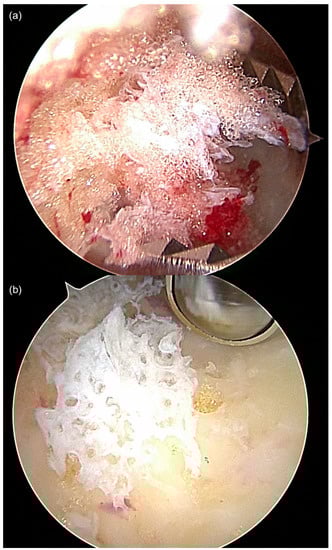

Figure 3.

Often, typical features of IOL ((a), fat tissue) and SBC ((b) membrane/cyst lining) were both observed in parallel in calcaneal ossocopy, suggesting a common pathogenesis and transitional forms of SBC and IOL. Both images are from the same ossoscopy (case 12).

Interestingly, two cases of IOL (cases 5 and 12) with characteristic preoperative MRI findings were histopathologically diagnosed as SBC. One additional case of MRI-diagnosed SBC showed membranous material with a histiocyte-resorptive reaction, consistent with SBC (case 11). Another case had material from a hemorrhaged lesion along with several bony particles (case 8), but no clear signs of lipoma of the bone. The absence of lipomatous tissue can be explained by the surgical technique. During endoscopic resection of IOL, the lipomatous tissue from the bone cavity is often washed out until a clear ossoscopic view is established and appropriate specimens are obtained (see Section 2.1). This problem was addressed later in the study (starting with case 13) by taking biopsies blindly once access to the tumorous lesion was established and prior to introduction of the scope. Our findings support the observation that SBCs can heal with fatty conversion of the cystic cavity, resulting in partly cystic remnants that may eventually transform to IOL (Figure 3). We agree with the findings of Tins at al. that at least part of the so-called IOLs are in fact, healed simple bone cysts [].

While MRI allows differentiation between cystic from lipomatous areas of the lesion, histopathological analysis is required to verify the correct diagnosis. Direct endoscopic visualization of the lesion can help to correctly assess mixed and transitional forms of SBC and IOL macroscopically (Figure 3). The high resolution of modern scopes (4K) and the magnification factor provide a much more detailed view of the findings during ossoscopy compared to open surgical resection. Thus, the tennis net-like membrane of SBC and other components of the lesion can clearly be identified.